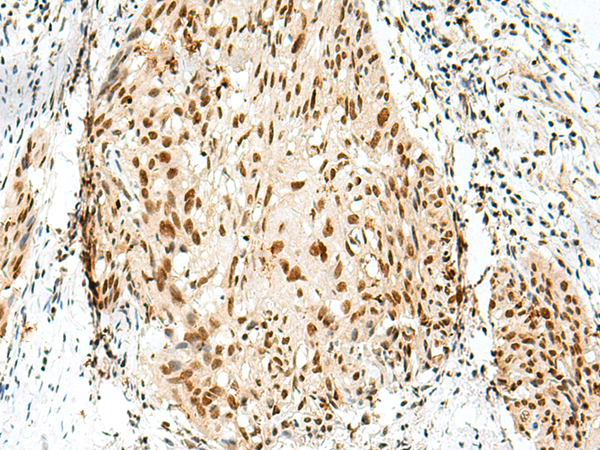

IHC positive control: |

Human esophagus cancer and Human tonsil |